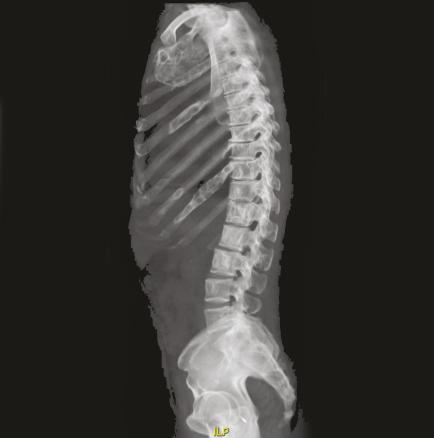

Les images IRM (fig. 1 et 2) du rachis montrent de multiples lésions vertébrales en hyposignal T1 et en hypersignal T2 hétérogène, atteignant à la fois les corps vertébraux et les arcs postérieurs. L’atteinte du rachis est ubiquitaire, prédominant en lombaire avec des zones lytiques et de signal liquidien.

Les images de scanner (fig. 3-5) mettent en évidence de multiples lésions soufflantes avec un aspect en verre dépoli de l’os trabéculaire refoulant la corticale ainsi qu’une érosion marquée de la corticale, sans réaction périostée, confirmant une dysplasie fibreuse polyostotique prédominant au niveau des côtes et du rachis, sans sténose canalaire.